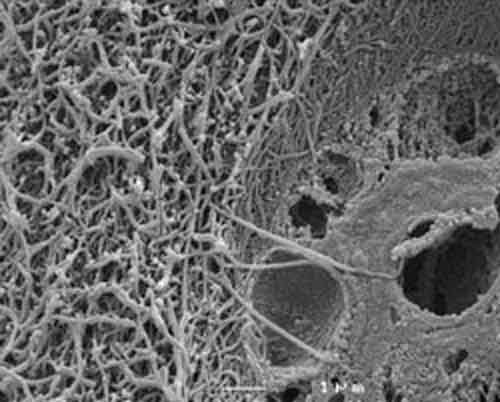

osteocalcina